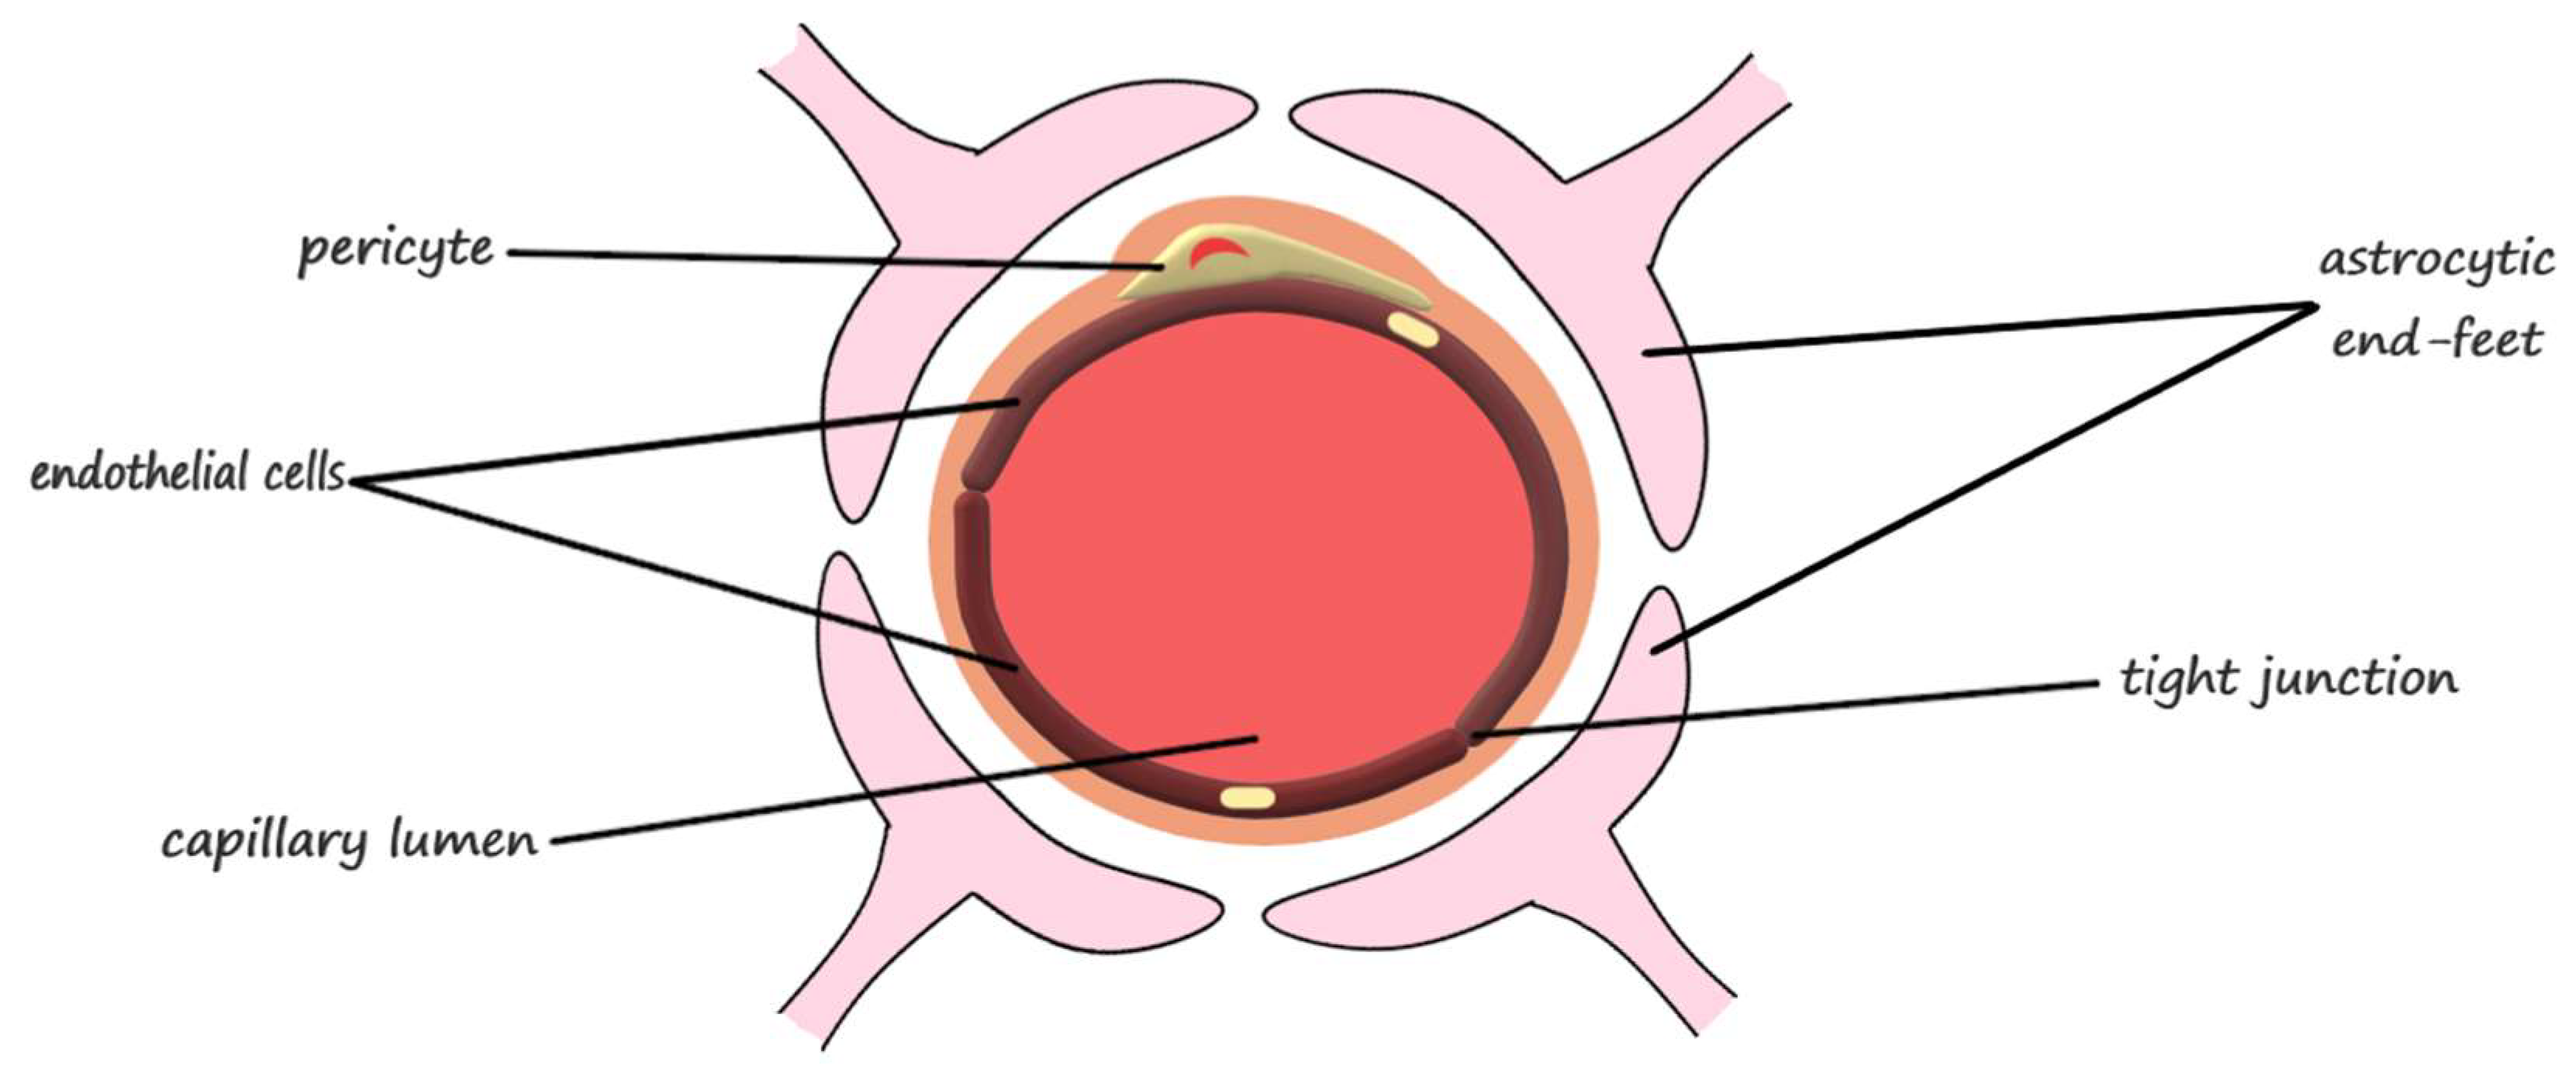

2. The Blood-Brain Barrier

2.1. The Anatomical Structure of the Blood-Brain Barrier

2.2. The Physiology of the Blood-Brain Barrier

| Blood-Brain Barrier Component | Function | |

|---|---|---|

| Neurovascular unit | endothelial cells | barrier function, transport of micronutrients and macronutrients, receptor-mediated signaling, leukocyte trafficking, and osmoregulation [31] |

| astrocytes | responsible for proper neuron and neurovascular unit functions and modulation of the blood-brain barrier phenotype [31] regulation of metabolism, the modulation of neuronal transmission, and brain development and repair [22] | |

| pericytes | regulation of endothelial cell proliferation, survival, migration, differentiation, and vascular branching [31] involved in angiogenesis, maintenance of the blood-brain barrier, regulation of immune cell entry to the brain, control of the cerebral blood flow, and constriction of capillaries in stroke [28] | |

| neurons | modulation of the blood-brain barrier permeability through neuronal-microvascular communications [31] | |

| extracellular matrix | modulation of the blood-brain barrier permeability and maintenance of tight junctions [31] | |

| Junctional complexes | occludin | ensures a high electrical resistance (tightness) of the tight junctions [31] |

| claudins | primary barrier function of the tight junctions [31] | |

| junctional adhesion molecules | mediation of the early attachment of adjacent cell membranes, involved in developmental processes [31] | |

| membrane-associated guanylate kinase-like proteins | modulation of the blood-brain barrier permeability [31] |